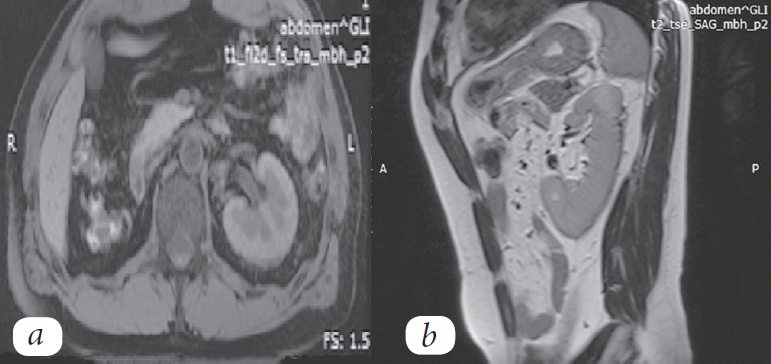

Через 6 месяцев после оперативного вмешательства (26.12.2017) пациенту выполнена МРТ брюшной полости. На фоне послеоперационных изменений признаков рецидивирования опухолевого процесса не обнаружено (рис. 6).

Рис. 6. МРТ с внутривенным контрастированием в аксиальной (а) и сагиттальной (b) плоскостях

Fig. 6. Magnetic resonance imaging with intravenous contrast agent administration in the axial (а) and sagittal (b) planes